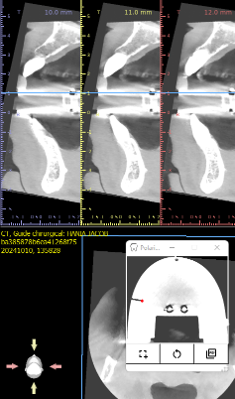

Visualization of the implant axis

The axis defined by the cone beam is materialized directly on the model.

- The application generates a 1:1 scale image

- with one point on plate A and one point on plate B.

In two-point geometry, a single straight line passes through: the axis of your implant

Polaris-implants generates points through which a straight line passes: the implant axis.

The virtual axis becomes a real axis, verifiable directly on the model.

Visualization of the implant axis on the model, accurately confirming the planning on the software.